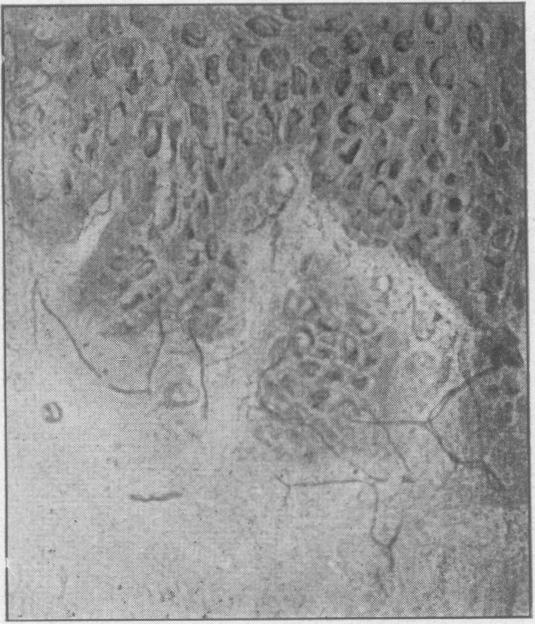

A comparative study of the innervation of the epithelium of the gum.

Proc R Soc Med. 1946 Apr;39(6):348-54. doi: 10.1177/003591574603900629.